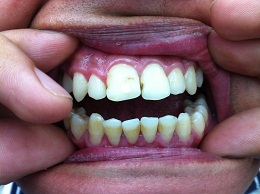

Клинический случай: пациент Е.,

20 лет, профессиональный спортсмен - единоборец, проходил курс лечения в

Стоматологической Клинике по поводу пародонтита средней степени тяжести (рис. 3 а - б.)

Рис. 3. Состояние пародонта до и после лечения

В связи с частым

возникновением аллергических реакций и других побочных эффектов при

использовании традиционных антисептиков, большой интерес вызывают природные

средства. В данном клиническом случае в комплексе с профессиональной гигиеной

осуществлялись аппликации

аппипрепаратом. Непосредственно после завершения курса альтернативной терапии

определялись нормализация цвета десны ее уплотнение, отсутствие кровоточивости.

Аналогичная положительная динамика клинического состояния околозубных

тканей выявлялась при обследовании полости рта почти у всех пациентов второй

группы.